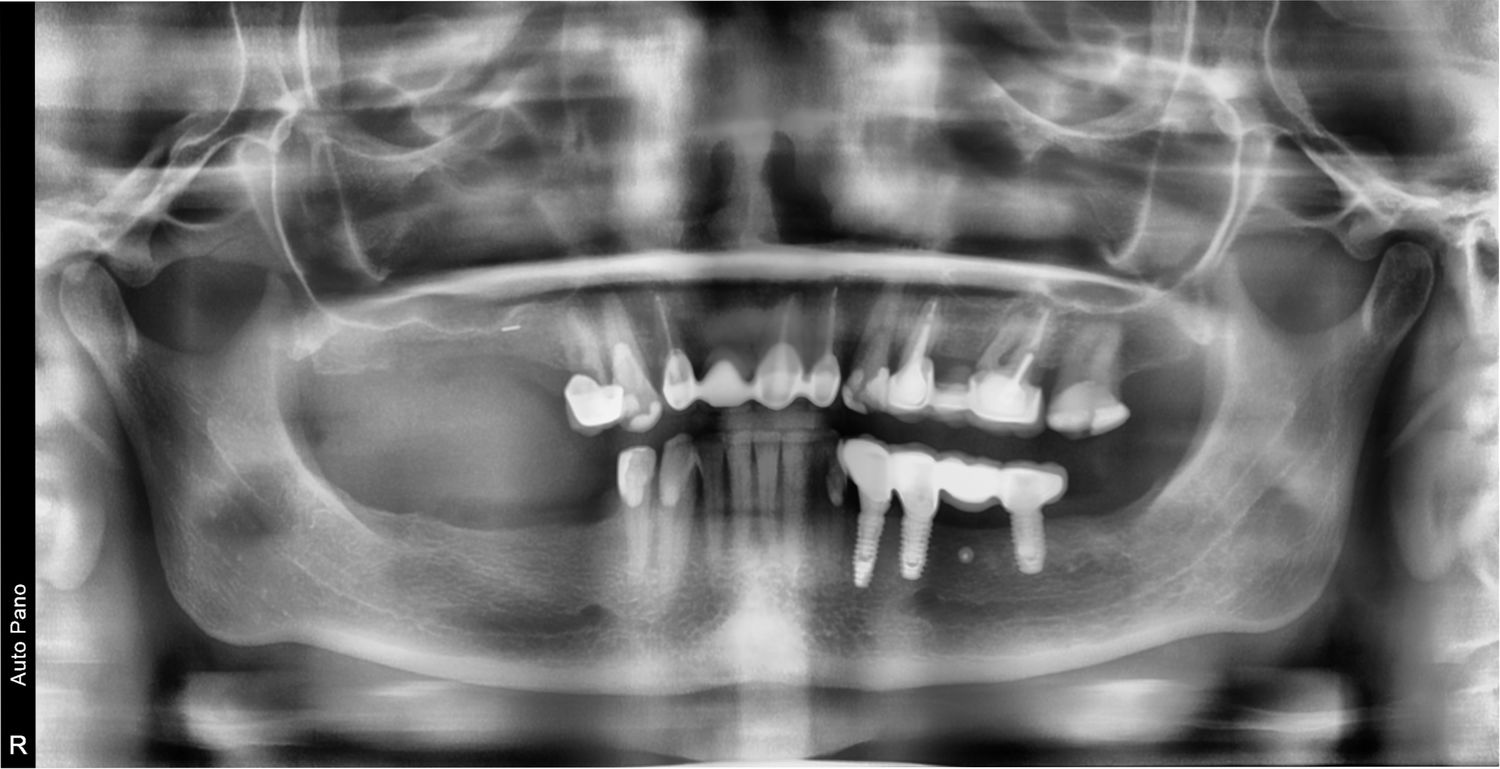

Пациентка направлена из другой клиники для проведения хирургической подготовки по созданию костных условий для будущей имплантации.

Пациентка 1968 года рождения направлена из другой клиники для проведения хирургической подготовки по созданию костных условий для будущей имплантации.

У пациентки наблюдается дефицит костной ткани на верхней челюсти справа и на нижней челюсти справа.

На верхней челюсти необходимо провести операцию открытого синус лифтинга и зафиксировать костный блок для увеличения объёма кости по ширине.

На нижней челюсти необходимо провести увеличение костной ткани по ширине за счет фиксации костных блоков.

На нижней челюсти с права в ретромолярной области взяли костный блок для дальнейшей его подготовки и фиксации.

Костный блок был разделен на 4 костных блока меньшего размера. Данные блоки были зафиксированы в 1 и 4 сегменте. Данная операция была проведена под седацией.